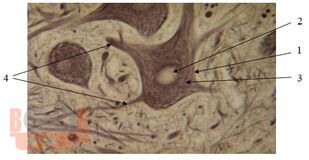

Учебно-методическое пособие составлено в соответствии с Федеральным государственным образовательным стандартом высшего образования, рабочей программой по дисциплине «Биология» по специальности 31.05.03 Стоматология. Освещены основные теоретические вопросы разделов биологии: биологии клетки, биологии развития. Даны методические рекомендации для выполнения практических работ, предназначенные для студентов 1 курса стоматологического факультета.